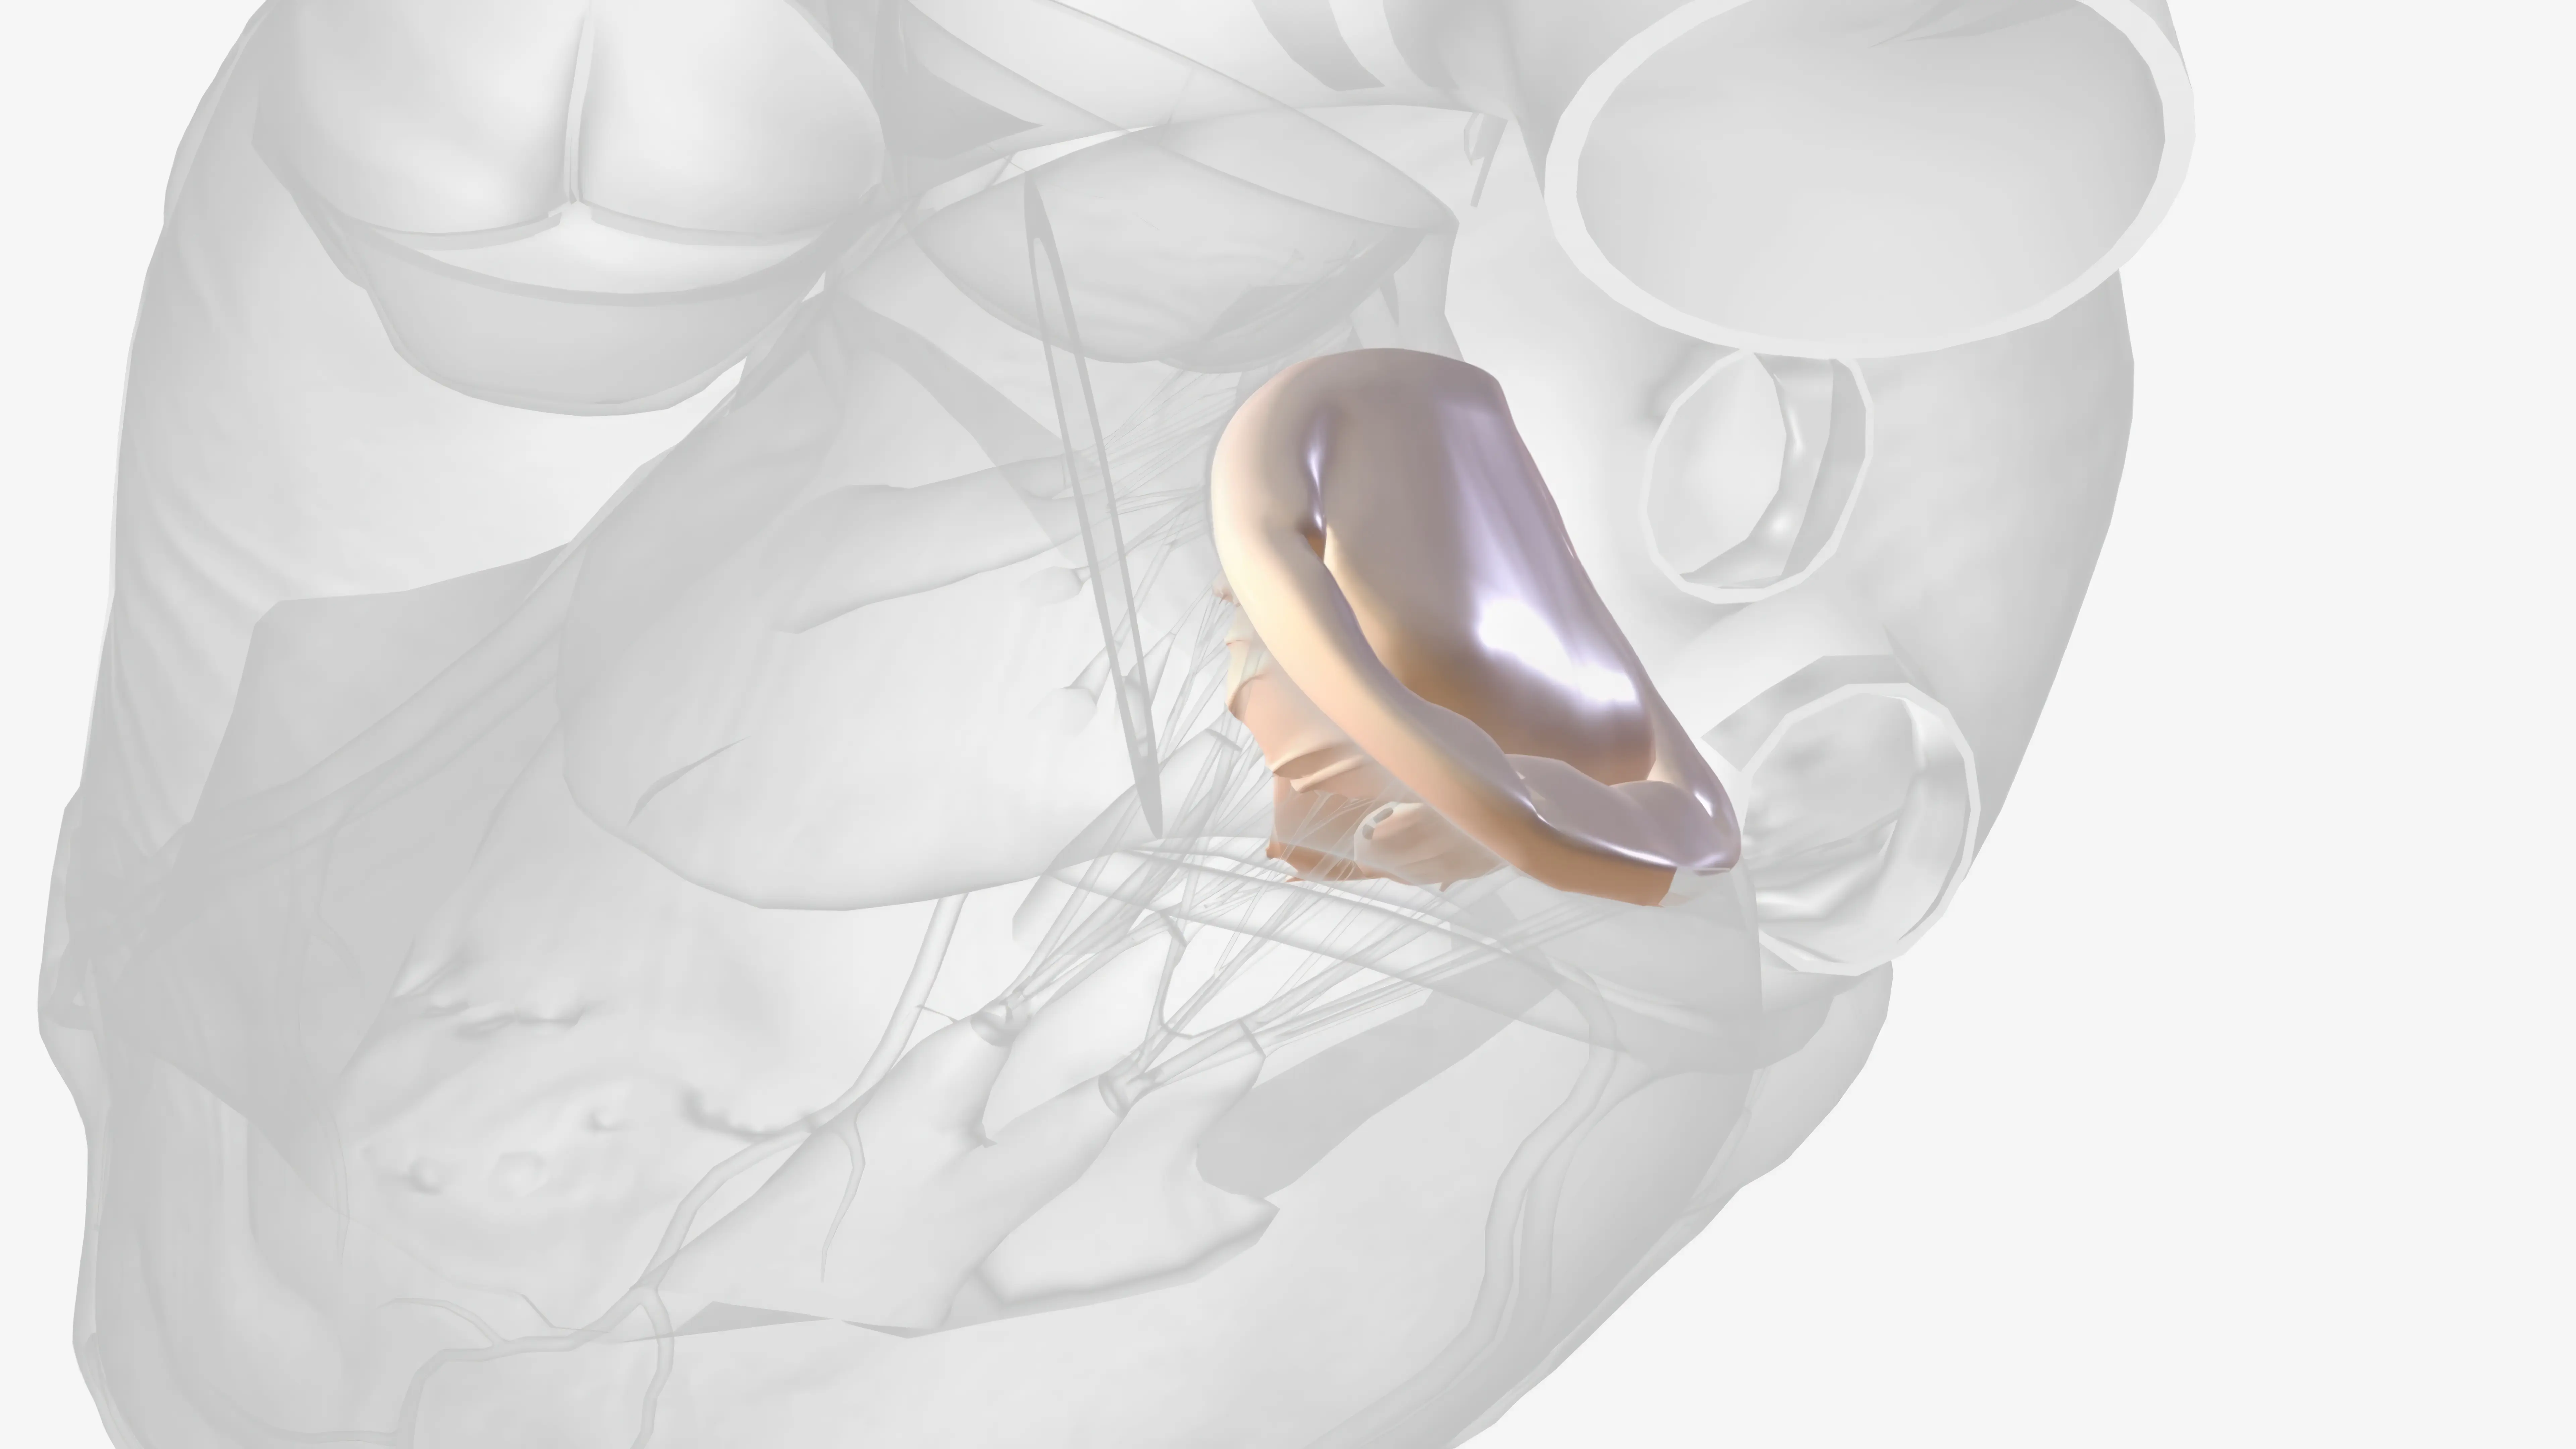

Anüloplasti ile Kalp Kapak Cerrahisinde Yenilikler

Anüloplasti ile kalp kapak cerrahisinde yenilikler: ring seçimi, transkateter ve invaziv teknikler, izlem ve komplikasyon yönetimini ele alıyoruz.